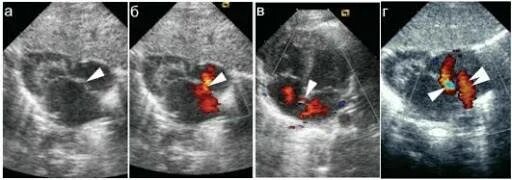

Окно в сердце у новорожденного